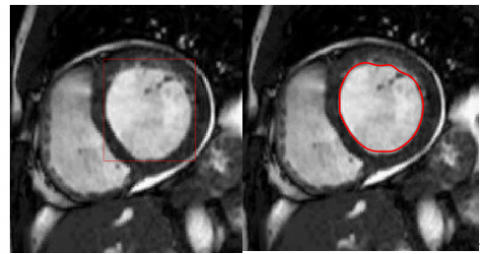

In Figure 11, we present the segmentation results applied to both MRI and ultrasound images, obtained using the DRLS (Distance Regularized Level Set) algorithm. The parameters used to segment MRI and ultrasound images were selected after several tests to achieve precise and rigorous segmentation that accurately defines the target contour.

(a) The cardiac ultrasound image

(b) The cardiac MRI image

(c) The ultrasound image

Figure 11. Segmentation results of MRI and echographic images

Using the parameters μ=0.04, λ=5, α=-1, σ=5 and 200 iterations, the segmentation of the cardiac ultrasound image demonstrates the effectiveness of the DRLSE algorithm in accurately detecting the edges of the cardiac wall, even in the presence of noise (Figure 11(a)). The moderate regularization ensured by μ=0.04 preserves the details of the contours, while λ=5 strikes a balance between contour attraction and stability. The parameter α=−1 enhances the algorithm’s ability to handle noisy regions, and σ=5 reduces noise while maintaining critical transitions in the image.

The set of parameters μ, λ, α, and σ allows for accurate and robust segmentation, proving the adaptability of the algorithm to the challenges posed by ultrasound images.

For the MRI heart image, the segmentation with the parameters μ=0.2, λ=1, α=1, σ=6, and 200 iterations demonstrates the DRLSE algorithm's ability to effectively highlight contrasts between different tissues, allowing for precise localization of the targeted contour (Figure 11(b)).

For the image shown in Figure 11(c), segmentation with the parameters μ =0.2, λ =5, α =-1, σ =6, and 200 iterations produces a satisfactory result. The segmented contours are both sufficiently sharp and well defined, while maintaining a certain smoothness that prevents the influence of noise. These parameter values provide an optimal compromise between fidelity to the image intensity data and contour smoothness, resulting in accurate segmentation while minimizing imperfections due to artifacts or noise.